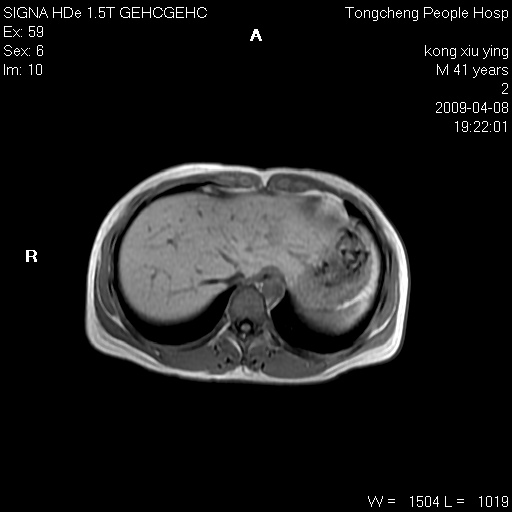

标题: CL1008:【经典】胆囊石榴籽样结石。

女,41岁。健康体检——彩超提示:胆囊显示不清。平素健康,无不适感。

腹部mr扫描及mrcp,图像如下: